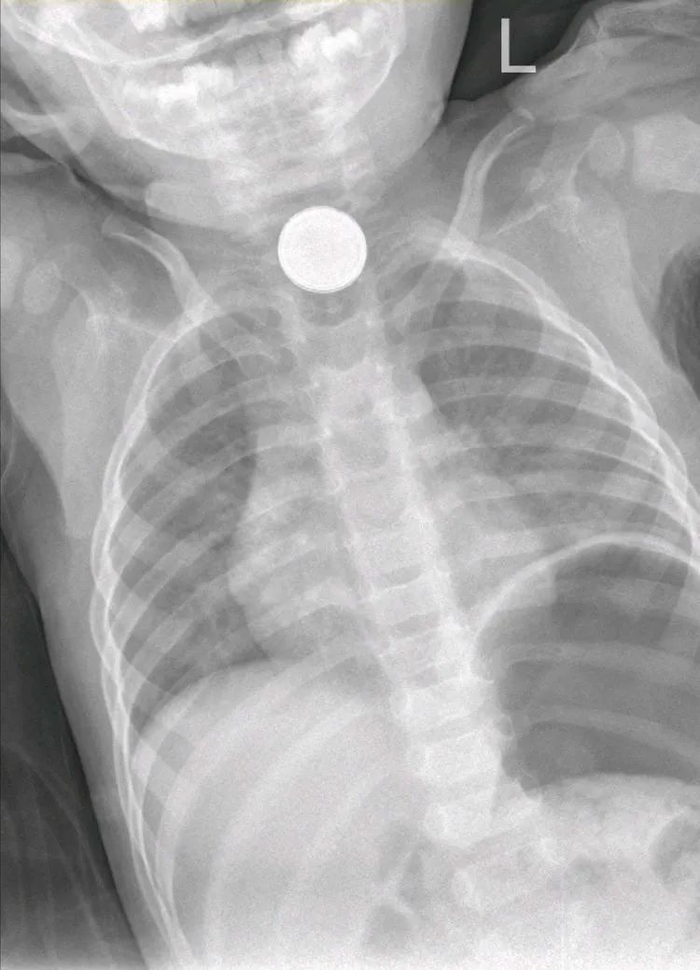

当晚接诊的是宁夏医科大学总医院儿童急诊,做了胸片检查,提示异物位于食道上段,于是请耳鼻喉头颈外科会诊,在局麻下做了食道镜检查,但电池的个头比加大,直径2厘米左右,接近5分钱硬币,而且孩子吞下去的是2枚电池,取出非常困难,甚至滑落到了更深的地方。

3月5日早晨,苏泽礼统筹指挥,多个科室密切配合,再次为孩子做胃镜探查,这一次,胃里的食物残渣已经排空了,可以清楚地看到电池,医生操作胃镜,利用网篮抓取电池后,慢慢往上提。但是到达咽喉部位时,卡住了,这里是食道生理狭窄处,而胃镜抓钳比较软,抓力不够,尝试了好几次都无法把电池取出来。

苏泽礼再次分析病情想办法:胃镜可以到达胃腔,但是抓力不够大,异物无法通过食道生理狭窄处。食道镜的抓钳比较硬,可以把异物从狭窄处取出,但是不能到达胃腔。那就来个接力赛吧,先上胃镜,把电池提上来,放在食道狭窄处,然后再上食道镜,把电池从狭窄处取出来。

方案一定,手术团队立即邀请耳鼻喉头颈外科副主任医师闫小会前来帮忙,在多个科室的配合协作下,两枚黏在一起的电池终于成功取出,危机解除了,大家都松了口气。